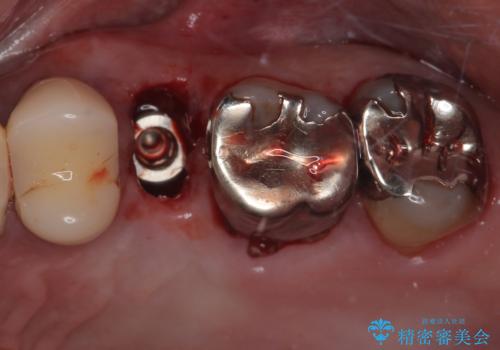

- 左上の小臼歯の被せものが外れてしまったことを主訴に来院された患者様の症例です。

診査・診断を行ったところ、

歯質の残存量(フェルール)が確保できない状態

歯根が短く、矯正治療で挺出を行っても将来的な予後が不良

と判断されました。

このようなケースでは、無理に被せ物をやり直しても再び脱離を繰り返したり、破折してしまう可能性が高く、長期的な安定は期待できません。そのため、今回は抜歯が最も妥当な治療選択と診断しました。

患者様の身体的・時間的負担を最小限に抑えるため、抜歯即時インプラントを選択しました。

この方法では、抜歯と同時にインプラントを埋入するため、

外科処置は1回のみ

治療期間の短縮

早期の機能・審美回復が可能

といったメリットがあります。

抜歯と同日にインプラントを埋入し、さらに仮歯まで装着するため、治療当日から見た目と噛む機能の回復が可能です。治療期間中も審美性と日常生活の快適さを維持できます。